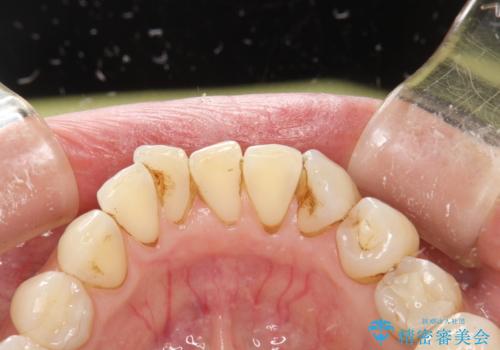

PMTCで歯と歯の間の細かいステインの除去

- 歯磨きでは取れない歯と歯の間の汚れが気になるとのことで来院されました。PMTC60分コースを行いました。

PMTCは、歯に付着した汚れを除去していくため、着色が気になる場合にも行うことができます。ご自身でのセルフケアだけで着色を落とそうとすると、逆に歯を傷つけてしまったり、精密に汚れを除去できないこともあります。また、日常生活で着色しやすい飲食物を避けたりすることはストレスに感じてしまったり、あまり現実的ではありません。

毎日丁寧に歯磨きをしていても、日常生活での飲食物などにより着色してしまうことはあります。PMTCでは、歯の表面の凸凹にミネラルを補給して、ツルツルの表面に仕上げます